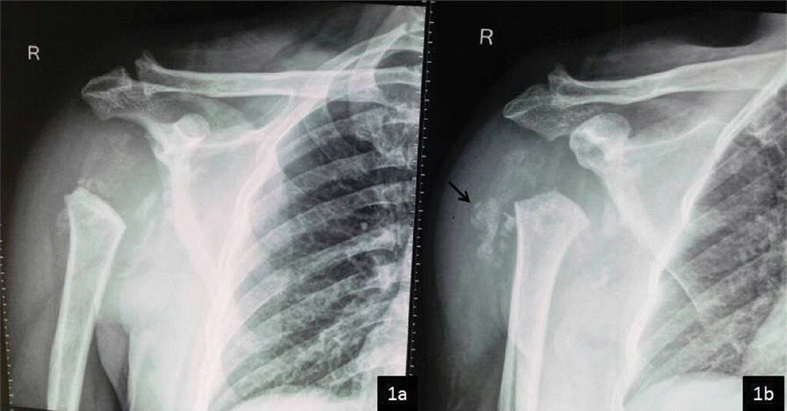

Plain radiography of right shoulder joint revealed destruction of entire head of humerus as well as multiple bony fragments surrounding the joint and overlying soft tissue swelling. The bone mineralisation of the uninvolved bones was normal [Table/Fig-1].

X-ray AP view of right shoulder joint a) and Oblique view b) shows complete destruction of humeral head, widening of gleno-humeral joint space, multiple osseous debris (black arrow) and overlying soft tissue swelling. Based on X-ray findings, diagnosis of Neuropathic joint was made.